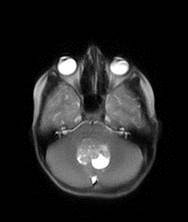

‘The Role of Diffusion Tensor Imaging in the Diagnosis of Paediatric Brain Tumours’ Heather Rose

We focus on the use of advanced magnetic resonance imaging (MRI) to help diagnose brain tumours in young patients. We measure the movement of water molecules within the brain to help identify any change in structure in and around brain tumours. An additional focus of the research project is the design of databases that store the MRI images and allow researchers from different universities to work on joint research projects.